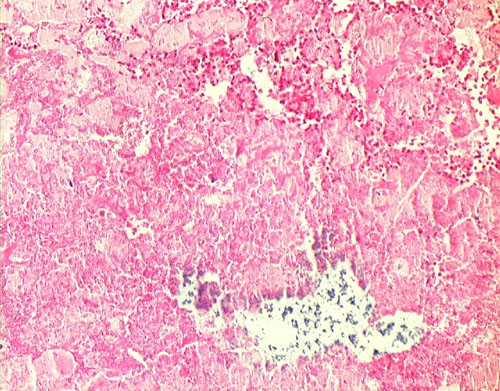

57. Healed Myocardial Infarction